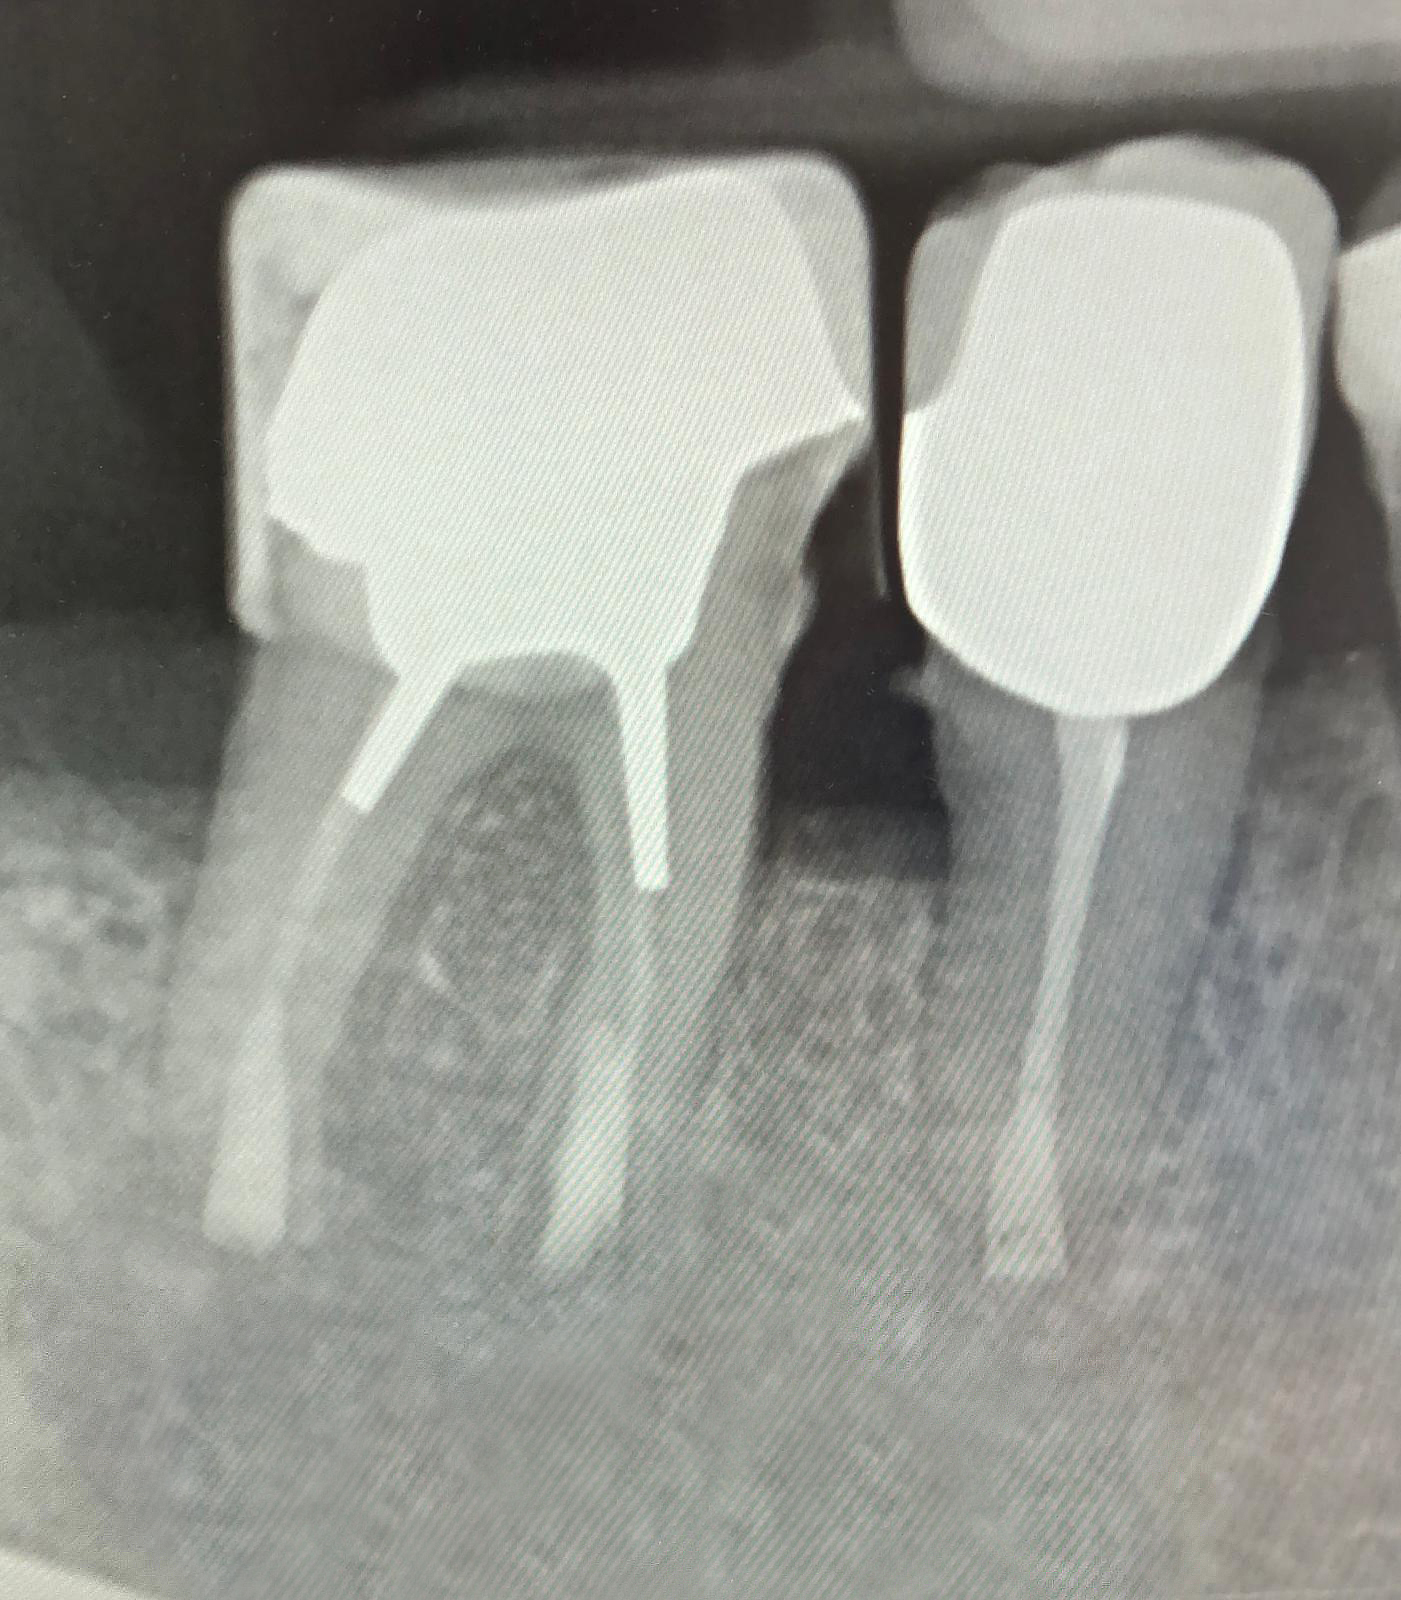

Röntgenaufnahme zweier ungehandelter Zähne mit Wurzelkanal Problemen. Die Aufnahmen zeigen die Zahnwurzeln und die umgebende Knochensubstanz.

Vorher

Röntgenaufnahme zweier behandelter Zähne mit Wurzelkanalfüllungen und Kronen. Die Aufnahmen zeigen die Zahnwurzeln, Wurzelfüllmaterialien und die umgebende Knochensubstanz.

Nachher